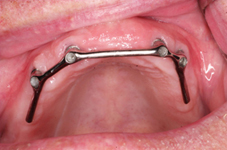

Bezzubá čelist je hlavní indikací pro ošetření pomocí implantátů. Zejména celkové zubní náhrady v dolní čelisti mají velice nízkou stabilitu a držení díky velkému úbytku kosti.

S pomocí zubních implantátů můžeme díky různým kotevním systémům (třmeny, kulové hlavy, Locatory) zajistit stabilitu a držení protézy nebo při použití většího počtu implantátů zhotovit pevné náhrady – můstky nalepené nebo našroubované na pevno na implantáty.

S těmito typy náhrad můžeme dosáhnout perfektní funkci, výbornou estetiku, fonetiku a současně zajistit u pacienta možnost dobré hygienickou péče a čištění, která je pro životnost implantátů velice důležitá.